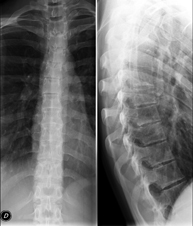

Tècnica que usa els raigs X a través de la qual s'obtenen imatges de la columna cervical per al seu estudi. Indicacions: traumatisme, dolor cervical. - RX Columna dorsal

Tècnica que usa els raigs X a través de la qual s'obtenen imatges de la columna dorsal per al seu estudi. Indicacions: traumatisme, mal d'esquena. - RX Columna lumbar

Tècnica que usa els raigs X a través de la qual s'obtenen imatges de la columna lumbar per al seu estudi. Indicacions: ciàtica, traumatisme, dolor lumbar. - RX Sacre-còccix

Tècnica que usa els raigs X a través de la qual s'obtenen imatges de tota la columna vertebral per al seu estudi, amb la valoració especialment de la presència d'escoliosi i dismetries pèlviques.

Tècnica que usa els raigs X a través de la qual s'obtenen imatges de tota la columna vertebral per al seu estudi, amb la valoració especialment de la presència d'escoliosi i dismetries pèlviques. - Telematria EEII (Extremitats Inferiors)